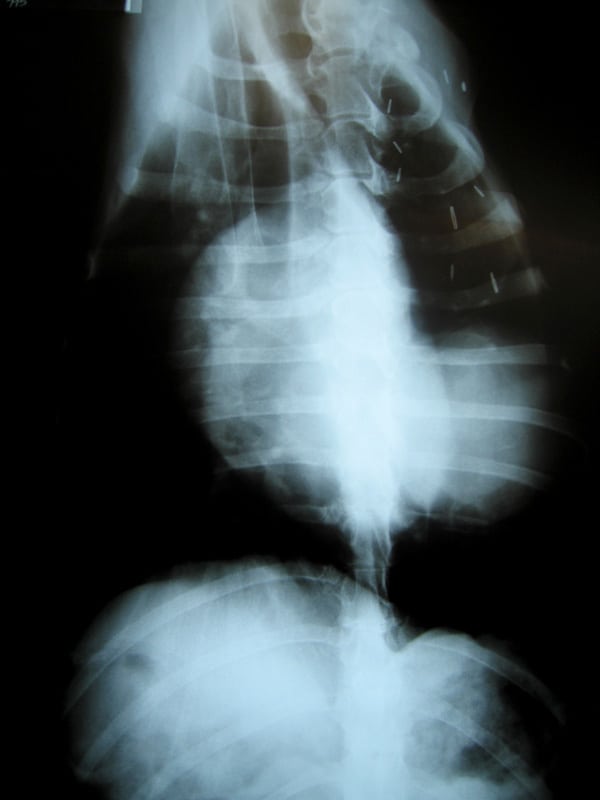

Dr. Mazzi listens to Jerry's lungsI went to the County Line Animal Hospital in La Habra today for a refill on my heartworm medicine since we’ll be on the road and off the beaten path for at least the next six months. While we were there, the nice vet convinced my people to get some x-rays of my chest.

Tomorrow we’ll get the results from tests on blood and urine samples they took from me. But the films clearly indicate that I do indeed have a lump in my lung. More of a mass really, about the size of a softball from the looks of things. But as I have proven all along, I’m a special case.

osteosarcoma metastasis xrayUsually, osteosarcoma metastasis presents itself as multiple legions throughout the lungs. The doctor expected to see a “snowstorm” on the x-rays. And I could tell my people did too, deep down inside. Instead, I appear to have a single large growth, which may or may not be operable.